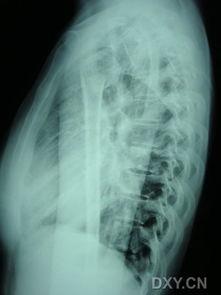

首先,得先了解一下肩关节半脱位。简单来说,就是肩关节的骨头和关节盂之间发生了轻微的错位。这种情况可能是因为肩部受到外力撞击、过度拉伸或者姿势不当等原因造成的。虽然听起来有点吓人,但其实很多情况下,肩关节半脱位是可以自行恢复的。